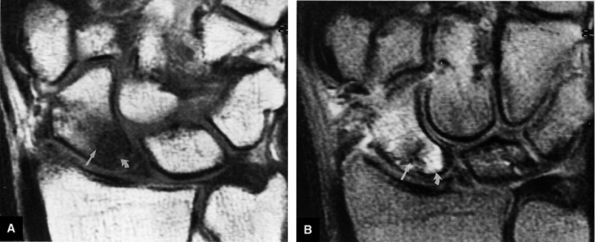

FIGURE 10.3 ● Identification of the dorsal fibers of the scapholunate and lunotriquetral ligaments on a coronal T1-weighted arthrogram. Although MR arthrography is frequently performed with FS, this decreases signal-to-noise. Routine FS PD FSE sequences are still used when performing MR arthrography, usually in the coronal and axial planes, to evaluate muscle and tendon pathology, chondral abnormalities, subchondral marrow edema, and noncommunicating ganglions. Postarthrogram sequences limited to FS T1-weighted sequences alone are inadequate for comprehensive diagnostic assessment.